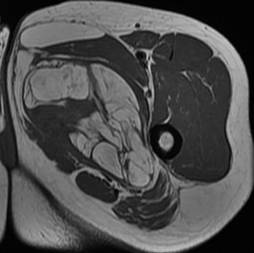

Liposarcome bien différencié. Noter la masse graisseuse, ayant une composante tissulaire (flèches) et des septas épais rehaussés après injection de gadolinium